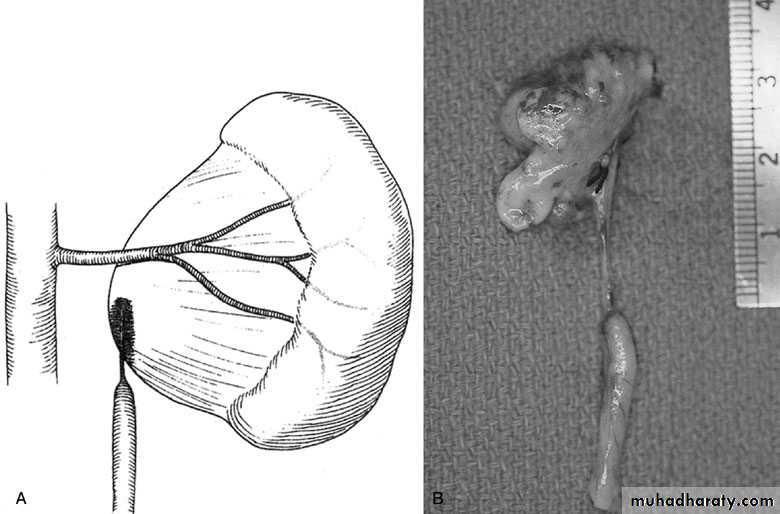

PUJ Obstruction – gross pathology

SURGICAL REPAIR including open surgical techniques, laparoscopic, & endoscopic approachesOpen & laparoscopic surgical techniques Anderson-Hynes dismembered pyeloplasty: excision of the pathologic UPJ & appropriate reanastamosis or flap technique or flap operation

Nephrectomy for non functioning kidney